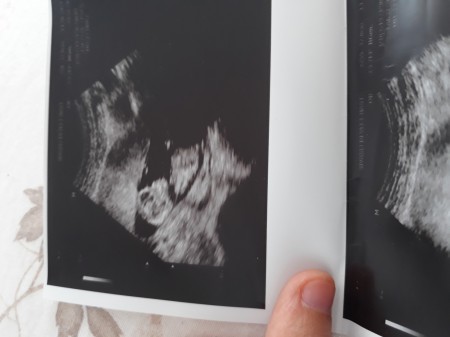

Cinsiyet tahmini yapabilir misiniz diyeceğim ama ben ayaklarını bile göremiyorum daha

Gebelik haftası 12+6